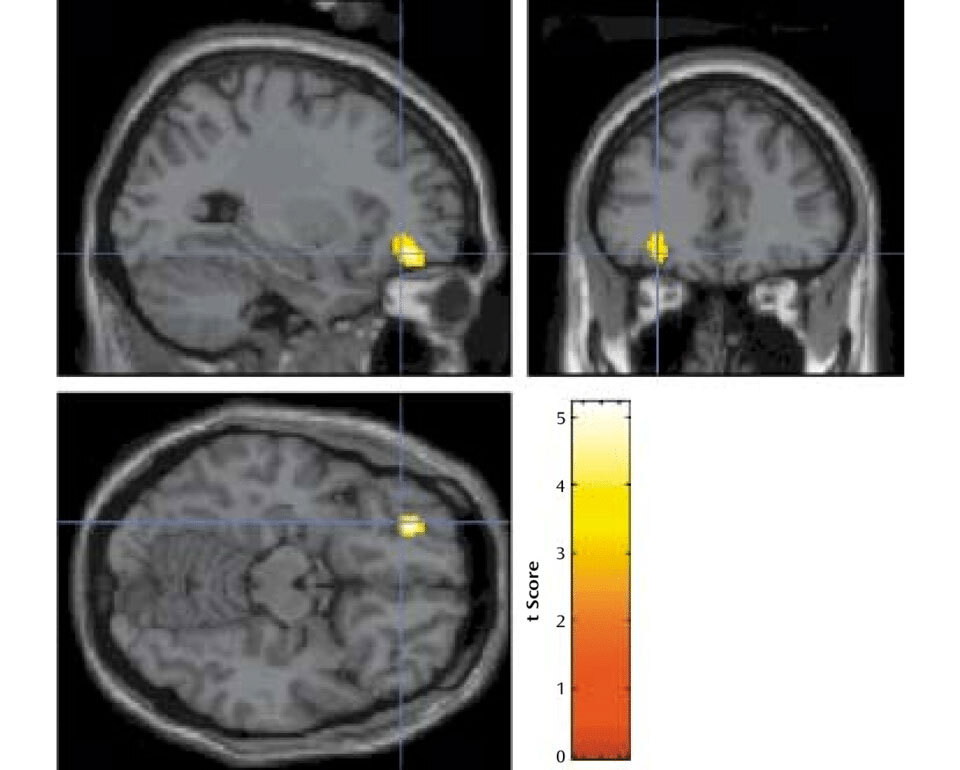

Через два месяца после начала программы, а затем еще через шесть месяцев участники — вместе с 246 другими студентами их программы — заполнили анкету, в которой ответили, с кем им нравится проводить свободное время. Оказалось, что у сдружившихся за восемь месяцев участников реакции в части левой орбитофронтальной коры — области мозга, участвующей в обработке субъективных ценностей, — более схожи, чем у дальних знакомых. Этот эффект оставался значимым даже после учета сходства во вкусах, основанного на оценке участниками своего удовольствия или интереса к видеороликам.

Через два месяца после начала программы нейронное сходство между друзьями и не-друзьями не отличалось, что позволяет предположить: изначально дружба может формироваться из-за близости, а со временем люди находят более близких друзей. Это подтвердилось, когда исследователи изучили, как менялись дружеские связи между двумя опросами. Участники, которые сблизились за этот период, демонстрировали значительно большее сходство в активности 42 областей мозга по сравнению с теми, кто отдалился друг от друга. Связь оставалась значимой даже после учета таких факторов, как возраст, пол и родной город.